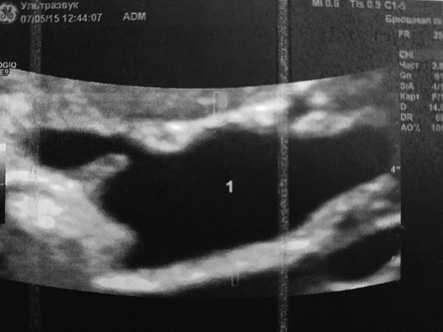

В клинике было выполнено повторное УЗИ печени и желчевыводящих протоков: структура печени однородная, эхогенность нормальная, размеры не увеличены. Сосудистый рисунок деформирован. Контуры ровные. Края без особенностей. Внутрипеченочные желчные протоки не расширены. Внепеченочные желчные протоки: отмечается сегментарное кистозное расширение внепеченочных желчных протоков ниже бифуркации — до 43 мм, на протяжении 58 мм. Воротная вена не расширена, проходима. Общая печеночная артерия не расширена, проходима. Печеночные вены не расширены, проходимы (рис. 1).

Рис. 1. Сегментарное кистозное расширение общего желчного протока.